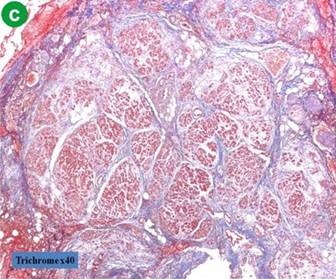

Assessment of Pancreas Consistency

In all cases, pancreatic duct diameter was measured after pancreatic transection by the operator. Parenchyma texture was divided into two groups based upon the extent of fibrotic changes in the resection margin. A fibrotic change was assessed by trichrome staining. Soft pancreatic parenchyma was characterized by the absence of fibrosis or slight thickness of perilobular fibrosis (up to 50 μm). Hard parenchyma was characterized by thick perilobular fibrosis greater than 50 μm (Figure 1).

Figure 1. Results of trichrome staining on the resection margin of the pancreas. a. b. Absence of fibrosis or slight thickness of perilobular fibrosis (less than, or equal to,50 μm ). c. d. Hard parenchyma was characterized by thick perilobular fibrosis greater than 50 μm. The purple color stained by trichrome show the component of fibrotic change in perilobular space. |